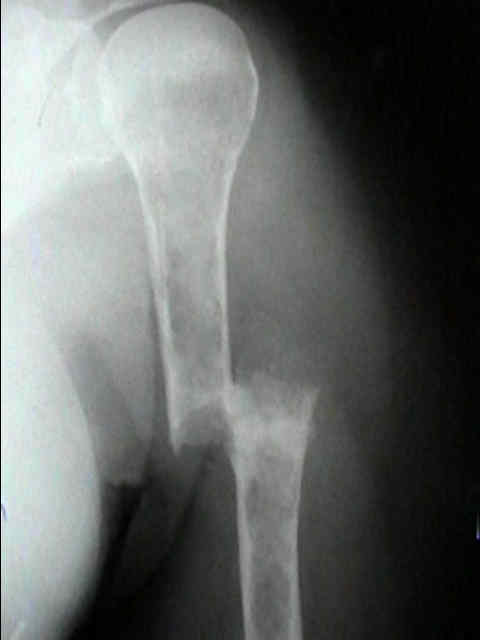

Se localiza, preferentemente, en los huesos donde existe médula ósea roja: vértebras, costillas, esternón, pelvis, cráneo y huesos largos (tercio proximal fémur y húmero).

Radiográficos:

Las radiografías normales pueden mostrar osteopenia difusa.

"Lesiones perforadas" o en "sacabocado" sin ninguna formación de nuevo-hueso circundante. Su diámetro es variable (hasta 5 cm.), redondas y múltiples.

Con el tiempo las lesiones pueden cambiar de osteopenia difusa a más permeativa con patrón destructivo apolillado, y a veces con expansión cortical.

La destrucción del hueso ocurre con poca o ninguna formación de hueso reactivo a menos que haya una fractura patológica.

Serie ósea:

El estudio del esqueleto es el estudio radiográfico más útil para hacer el diagnóstico.

Los mielomas pueden presentarse como lesión solitaria o más normalmente como un tumor difuso, involucrando múltiples huesos, incluyendo vértebras, cráneo, pelvis y fémures.